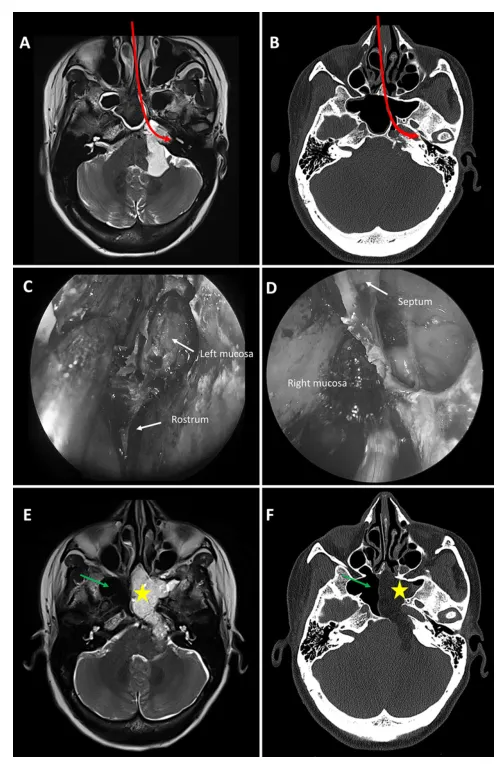

图1. 保留一侧蝶窦粘膜的微创入路示意图。

A 和 B:术前轴位T2加权MR图像(A)和CT扫描(B)显示一例以岩斜区为中心的左侧软骨肉瘤。蝶窦高度气化,侧隐窝明显。选择右侧对侧单鼻孔入路结合粘膜缝合“筷子”技术切除肿瘤,保留右侧蝶窦(红色箭头)。C 和 D:术中内镜视图显示保留的右侧蝶窦粘膜,其从鼻中隔轻柔剥离并牵开,为磨除ICA后方的岩尖创造了一个通道。E 和 F:术后轴位T2加权MR图像(E)和CT扫描(F)显示右侧蝶窦(绿色箭头)被保留,手术腔内填充脂肪,左侧蝶窦(黄色星号)被清空。